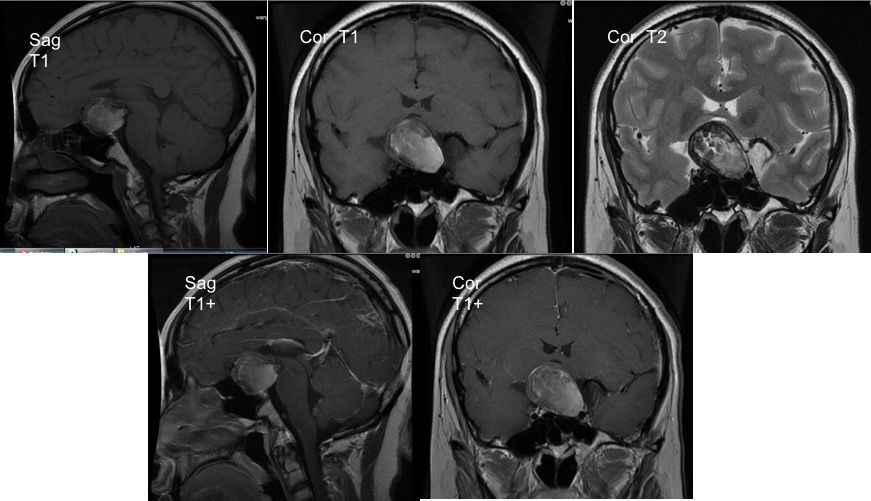

垂体增强MRI:鞍区见巨大类圆形混杂异常信号病灶,界限清,大小约39.7mm*28.4mm*33.2mm,以等短T1、稍长T2信号为主,病灶内信号不均匀,增强扫描病灶边缘局部轻度强化。垂体明显受压变扁,垂体柄及视交叉显示不清。第三脑室前下部受压,且鞍底骨质受压变薄。双侧海绵窦区结构未见异常 (图2)。

图2. 垂体MRI检查,显示鞍内肿瘤向鞍上发展,边界清